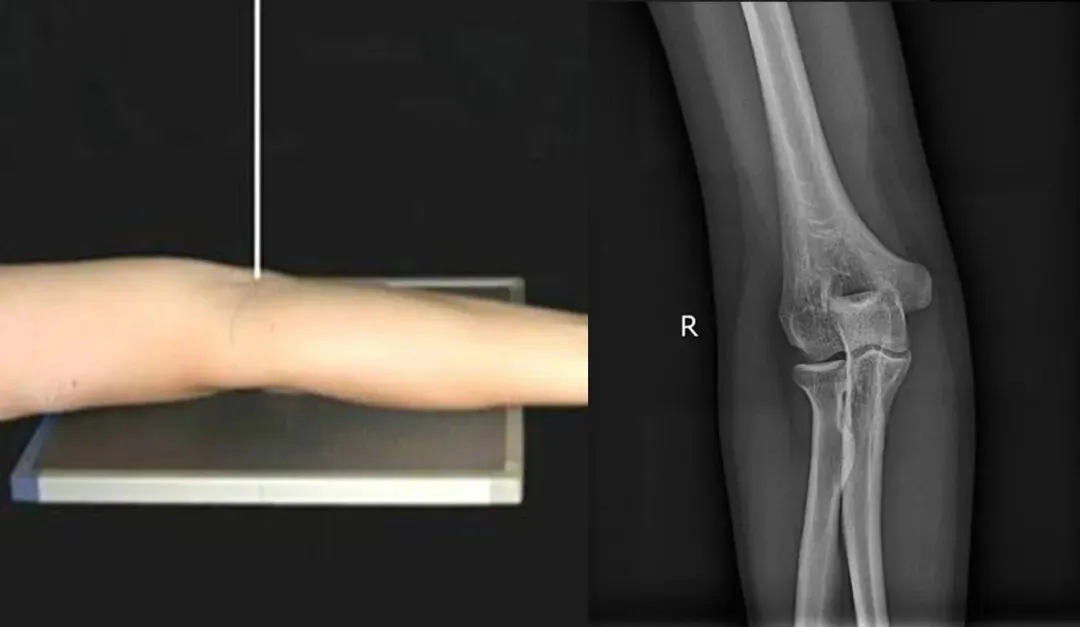

三、肘关节侧位

1.摄影要点:

(1)受检者面向摄影台侧坐,曲肘成90°~120°,肘关节内侧贴近摄影台面;

(2)手掌面对受检者,拇指在上,尺侧朝下,成侧位姿势,肩部下移,尽量接近肘部高度;

(3)照射野和探测器上缘包括肱骨下段,下缘包括桡尺骨上段;

(4)源-像距离为100cm;

(5)中心线对准肘关节间隙,垂直射入探测器中心。

2.肘关节侧位片标准影像显示:

(1)肱骨远端与桡尺骨近端成90°~120°;

(2)尺骨与肱骨的关节间隙显示明确、锐利;

(3)肱骨内外髁重叠,呈圆形投影;

(4)肘关节诸骨纹理清晰,周围软组织层 次分明。

五、桡尺骨侧位

(1)受检者面向摄影台就坐,曲肘约成90°;

(2)前臂呈侧位,尺侧贴近摄影床面,肩部下移,尽量接近肘部高度;

(3)源-像距离为100cm;

(4)中心线对准前臂中点,垂直射入探测器。

2.桡尺骨侧位片标准影像显示:

(1)影像显示桡骨、尺骨、腕关节和(或)肘关节侧位影像;

(2)布局合理,图像包括腕关节和(或)肘关节,至少应包括一个关节,桡尺骨呈侧位影像;

(3)清晰显示骨小梁和周围软组织。

六、为何尺桡骨正位需伸直肘部拍摄,而侧位则弯曲肘部90°拍摄(仿如肘关节正侧位)?